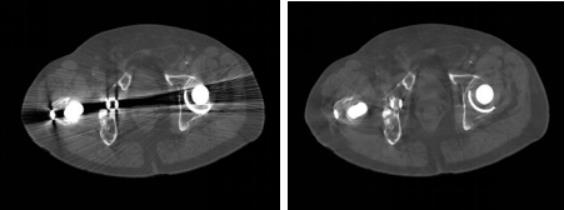

采用Smart MAR 基于原始数据的智能去金属伪影技术,对内部有金属植入物的患者也能做到图像精准定位,从更深层次的根源消除金属伪影,使有金属植入物患者的图像更清晰,不受到金属内固定物的伪影干扰。

△无Smart MAR(上)和有Smart MAR(下)